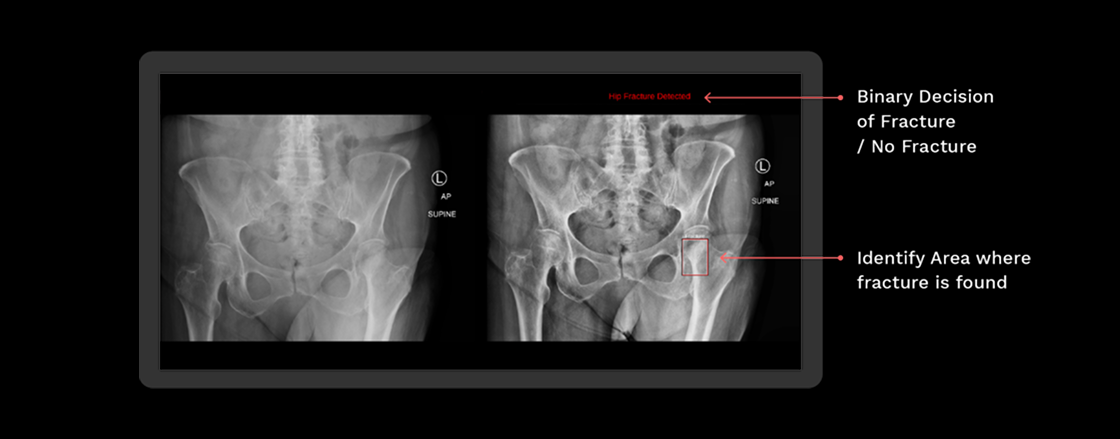

Rbfracture™

AI-powered, automatic detection of trauma-related findings

Benefits of using RBfracture™

Supports trauma

reads 24/7

Improved diagnostic

accuracy

Suggested diagnosis

within seconds